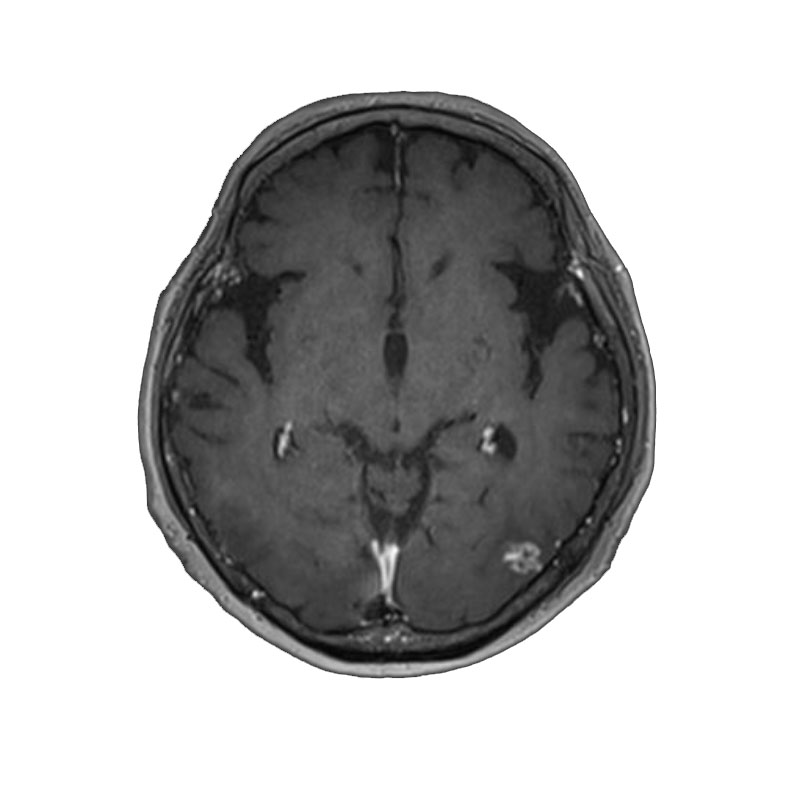

脳動静脈奇形

血管塞栓術

松田/濵田/元永